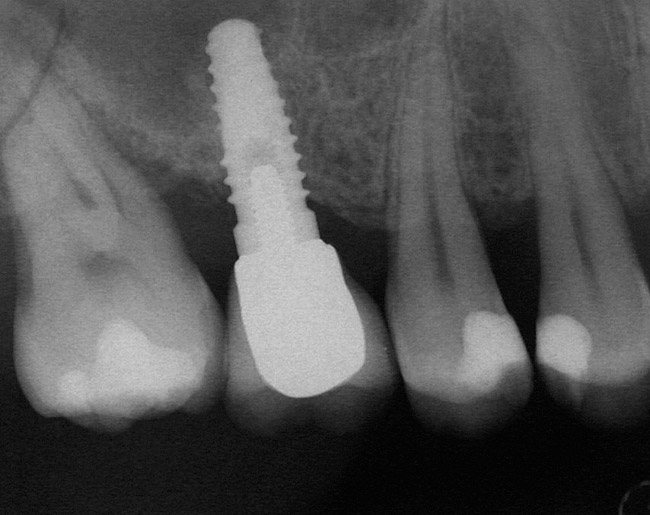

A 45-year-old female was referred for implant placement and prosthetic treatment in the area of tooth No. 24. The tooth had been extracted 4 years prior; the patient did not wear any denture thereafter. The radiograph revealed adequate bone height and a 5-mm to 6-mm ridge at the crest (Figure 2). It was decided to place a 11.5 mm in length, 3.75 mm in diameter Tapered Screw-Vent® implant (Zimmer Dental, www.zimmerdental.com) using the alveolar remodeling technique in the area of tooth No. 24.

Figure 2  Preoperative view of the area around tooth No. 24. On the left, a previously placed implant abutment is visible.

Figure 2